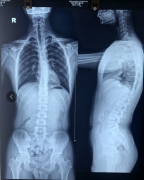

15岁少年军人梦差点被破灭,凶手竟然是它!

一向风度翩翩的安主任,刚才在门诊竟然生气了。这到底是怎么回事呢?赶紧跟我来看看吧! 原来他今天接诊了一位脊柱侧弯的患者飞飞,患者说自己从小喜欢看军旅题材的电视和电影,